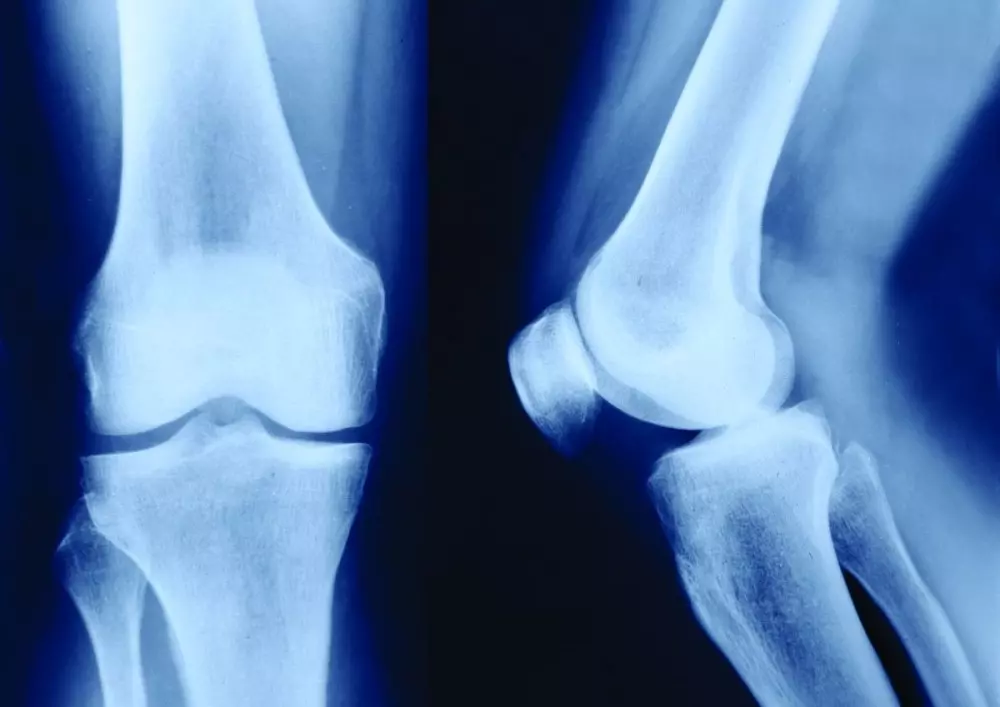

Rekonstrukcja więzadła krzyżowego

Zachęcamy także do lektury artykułu pt. „Artroskopowa rekonstrukcja więzadła krzyżowego przedniego. Zasady fizjoterapii część I”. Zerwanie więzadła krzyżowego przedniego często dotyka sportowców, jednak także osoby nieaktywne fizycznie i starsze są na nie narażone. Ze względu na to, że nie ma szans na samodzielne zagojenie się tego urazu, stosowana metoda leczenia to rekonstrukcja więzadła krzyżowego, najczęściej przeprowadzana artroskopowo.